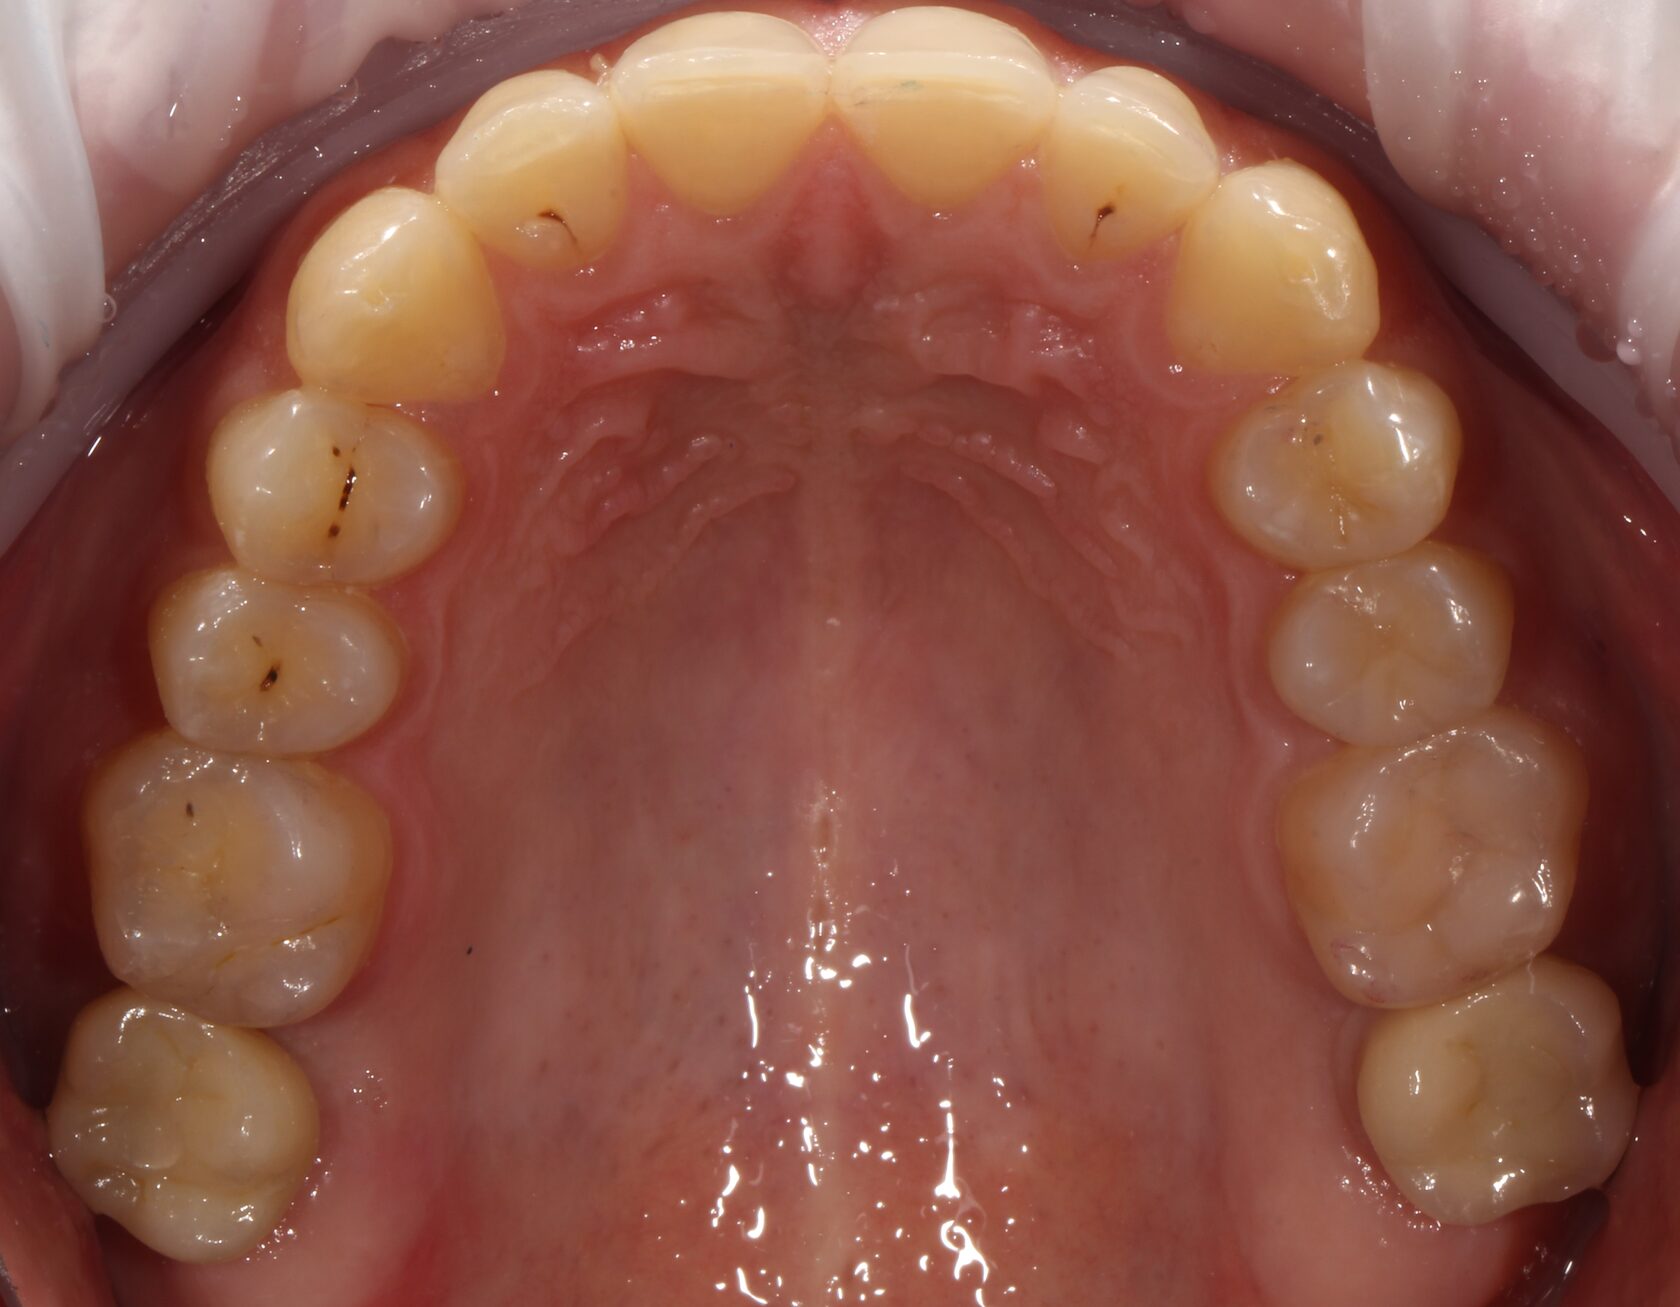

Результат комплексного лечения пациента командой врачей нашей клиники.

Выполнено:

1 Комплексная диагностика и планирование лечения.

2 Лечение всех зубов пораженных кариозным процессом и замена всех несостоятельных пломб.

3 Удаление зубов мудрости.

4 Установка дентальных имплантатов в зоны удаленных зубов.

5 Финальное рациональное протезирование с опорой на дентальные имплантаты.

6 Динамическое наблюдение с 2022 года.